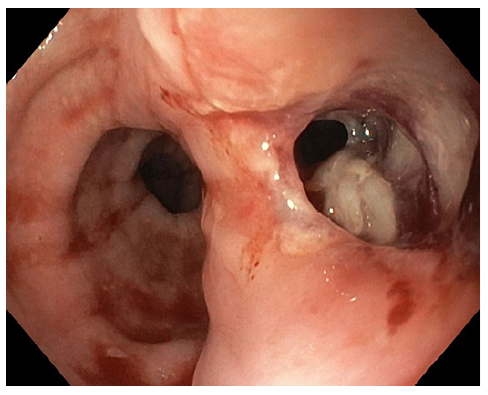

Upper digestive endoscopy was performed, with CO2 insufflation in the operating room in the presence of the general surgery team, under orotracheal intu-bation, and it identified a bone perforation 23 cm from the upper dental arch - the bone was removed with forceps only after unlocking and deflating the endotracheal tube cuff due to space conflict. After extracting the bone, a 15 mm esophageal perforation (shown in Fig. 2) was closed with 4 through-the-scope (TTS) clips (shown in Fig. 3).